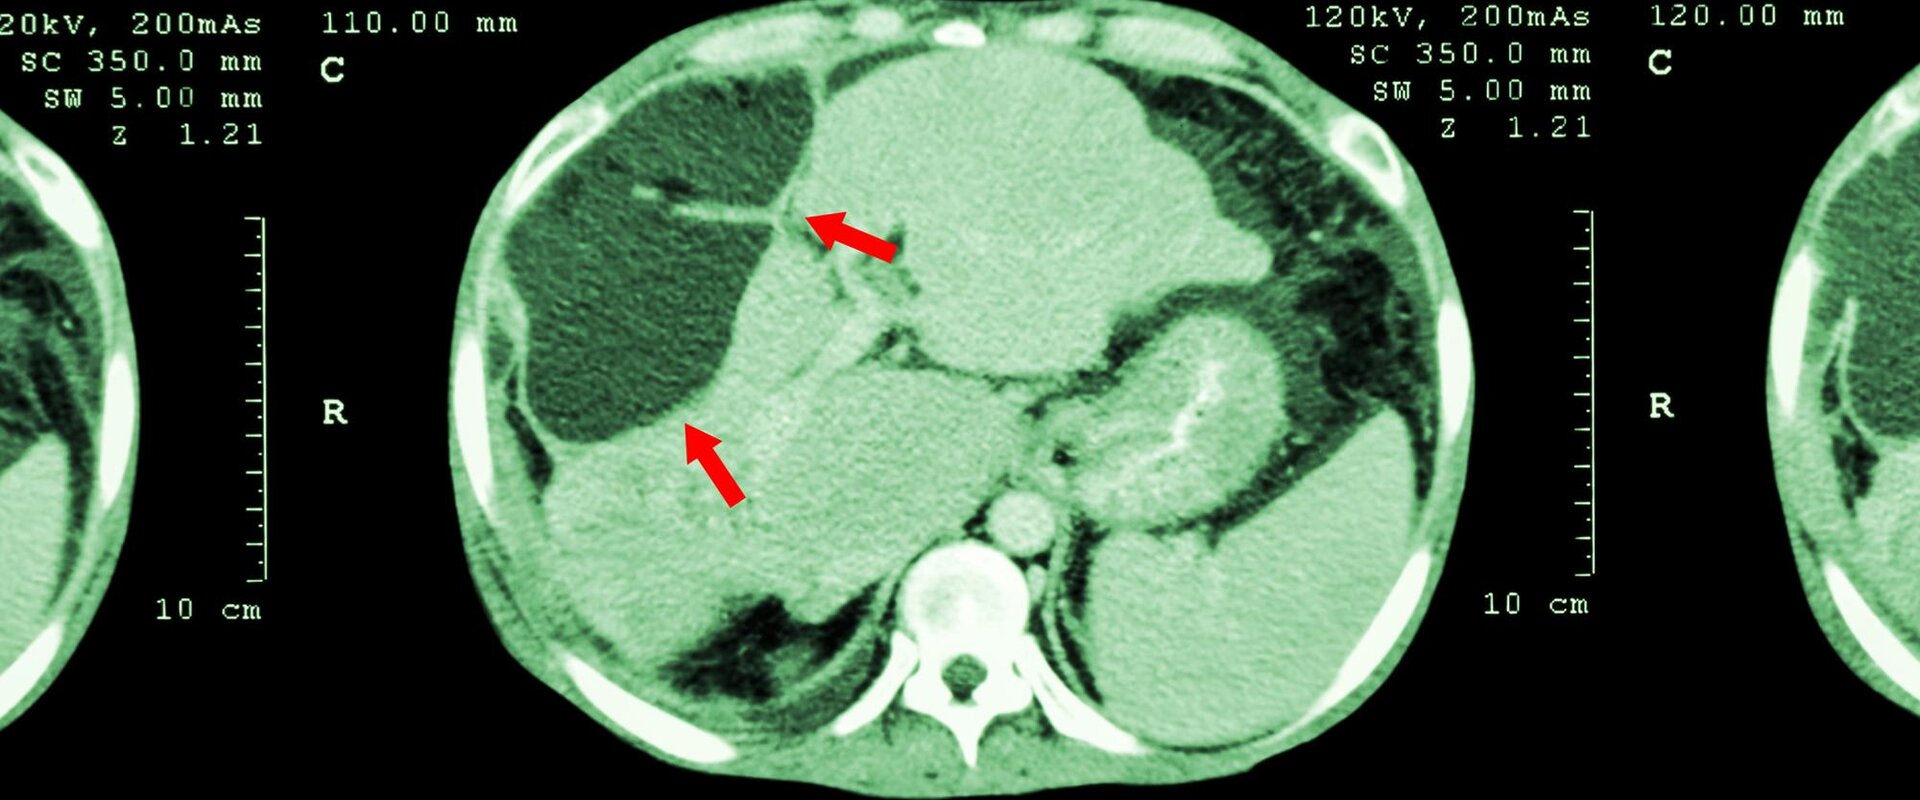

For many years molecular radiotherapy (MRT) has been used for palliative care of cancer patients, but it has great potential to become a potent first line cancer treatment. The therapy uses radioactive drugs to target specific tumour locations, for example by injection of radioactive microspheres into tumours in the liver via its artery.

The EMRP project Metrology for molecular radiotherapy (MetroMRT) developed a radiotherapy dose measurement method for radioactive microspheres based on accurately monitoring radioactivity both at the point of administration and at the tumour site. The project identified issues that hamper the activity measurement of radioactive microspheres, such as variations in the dimensions of vial wall thickness and microsphere solution density. The work enabled improved radioactivity measurement traceability, and established a robust link to conventional activity measurements in the clinic for Yittrium-90 in solution before the microspheres are administered to the patient. The administered activity is a critical parameter in the use of Yittrium-90 microspheres to treat liver cancer patients.